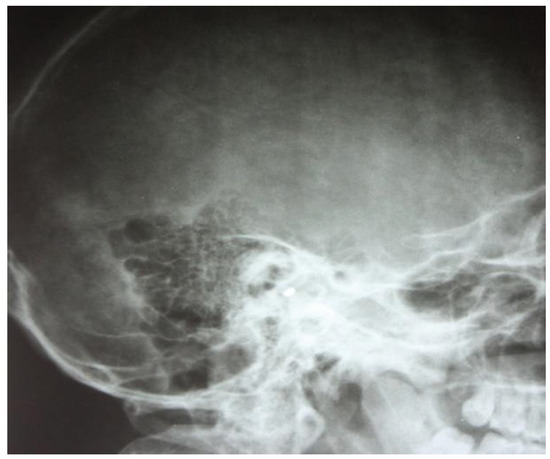

3.1.1. Conventional Radiology